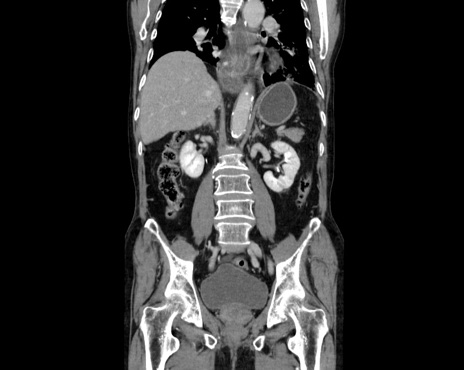

症例26(冠状断像)

横断像

【症例】80歳代男性

【主訴】嘔吐

【現病歴】昨晩2回嘔吐あり、今朝になっても嘔吐あり。来院。

【既往歴】胃潰瘍

【身体所見】意識清明、BT 37.6℃、BP 166/95mmHg、HR 100bpm、SpO2 97%、腹部:平坦・軟、腸蠕動音聴取良好、圧痛なし。

【データ】WBC 21900、CRP 1.4